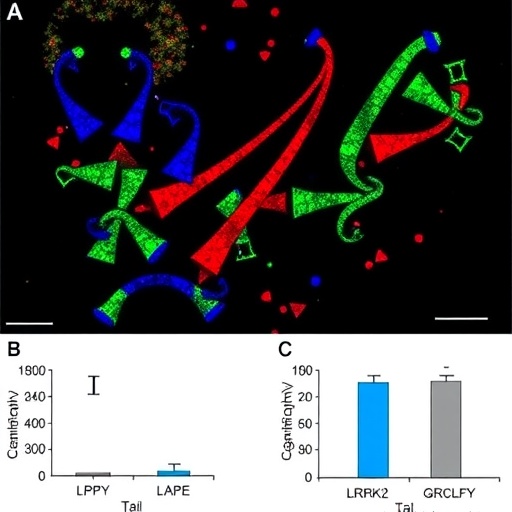

The research team employed rats genetically engineered to carry the LRRK2 R1627P mutation, exposing these animals to environmental factors known to induce inflammation, such as bacterial endotoxins and dietary toxins. Their findings demonstrated a pronounced increase in gut-derived chronic inflammatory markers compared to controls, along with a striking elevation in pathological α-synuclein accumulation. α-Synuclein, a presynaptic neuronal protein prone to misfolding and aggregation, forms the core of Lewy bodies—intracellular inclusions traditionally seen in brains of PD patients. Importantly, the study pinpoints the gut as an early site of α-synucleinopathy triggered or exacerbated by genetic and environmental interactions.

Moreover, by comparing wild-type rats to those carrying the R1627P mutation, the researchers found a clear gene-environment synergy that intensifies disease manifestation. Environmental insults alone induced moderate inflammation and protein aggregation, whereas the mutation dramatically amplified these phenotypes, underscoring the importance of genetic susceptibility in modulating disease risk. This nuanced understanding deepens the challenge of unraveling idiopathic PD cases that may involve subtle or unknown genetic variants influencing environmental response.